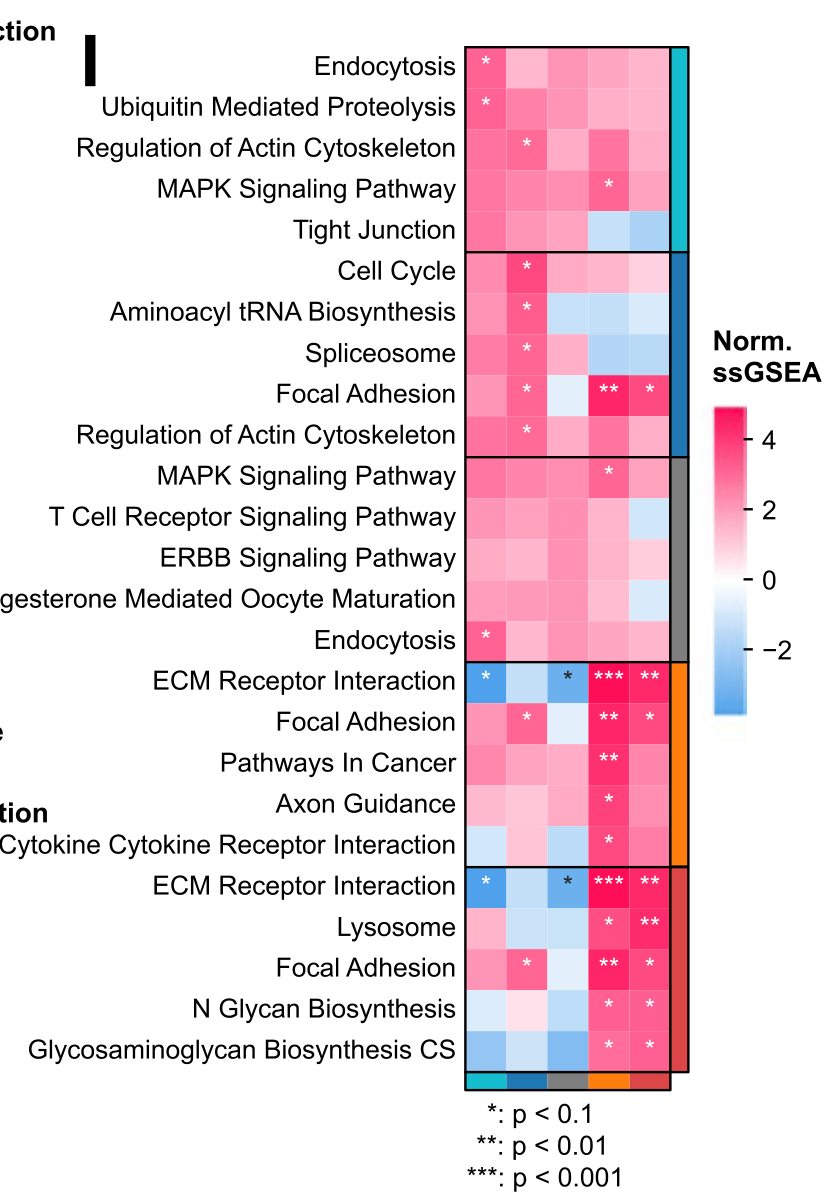

Which cancer-related pathways are enriched in different tumor regions?

Dong et al., 2021

Deciphering spatial domains from spatially resolved transcriptomics with an adaptive graph attention auto-encoder

Condition Dimension

N/A

Data Components

Biological AnnotationGene Expression Matrix

Data

Modality

Imaging-based

Resolution of observation

Sub-cellular

Visualized Elements

Observation

Biological

Tissue

Abstraction

None

Chart Type

Flourescence tissue image

Communicative/Contextualization

Annotation

Comparative Design

None

Layout

Spatial : Physical

Scalability Strategy

None (Item-level)

What is the anatomical structure of the tissue?